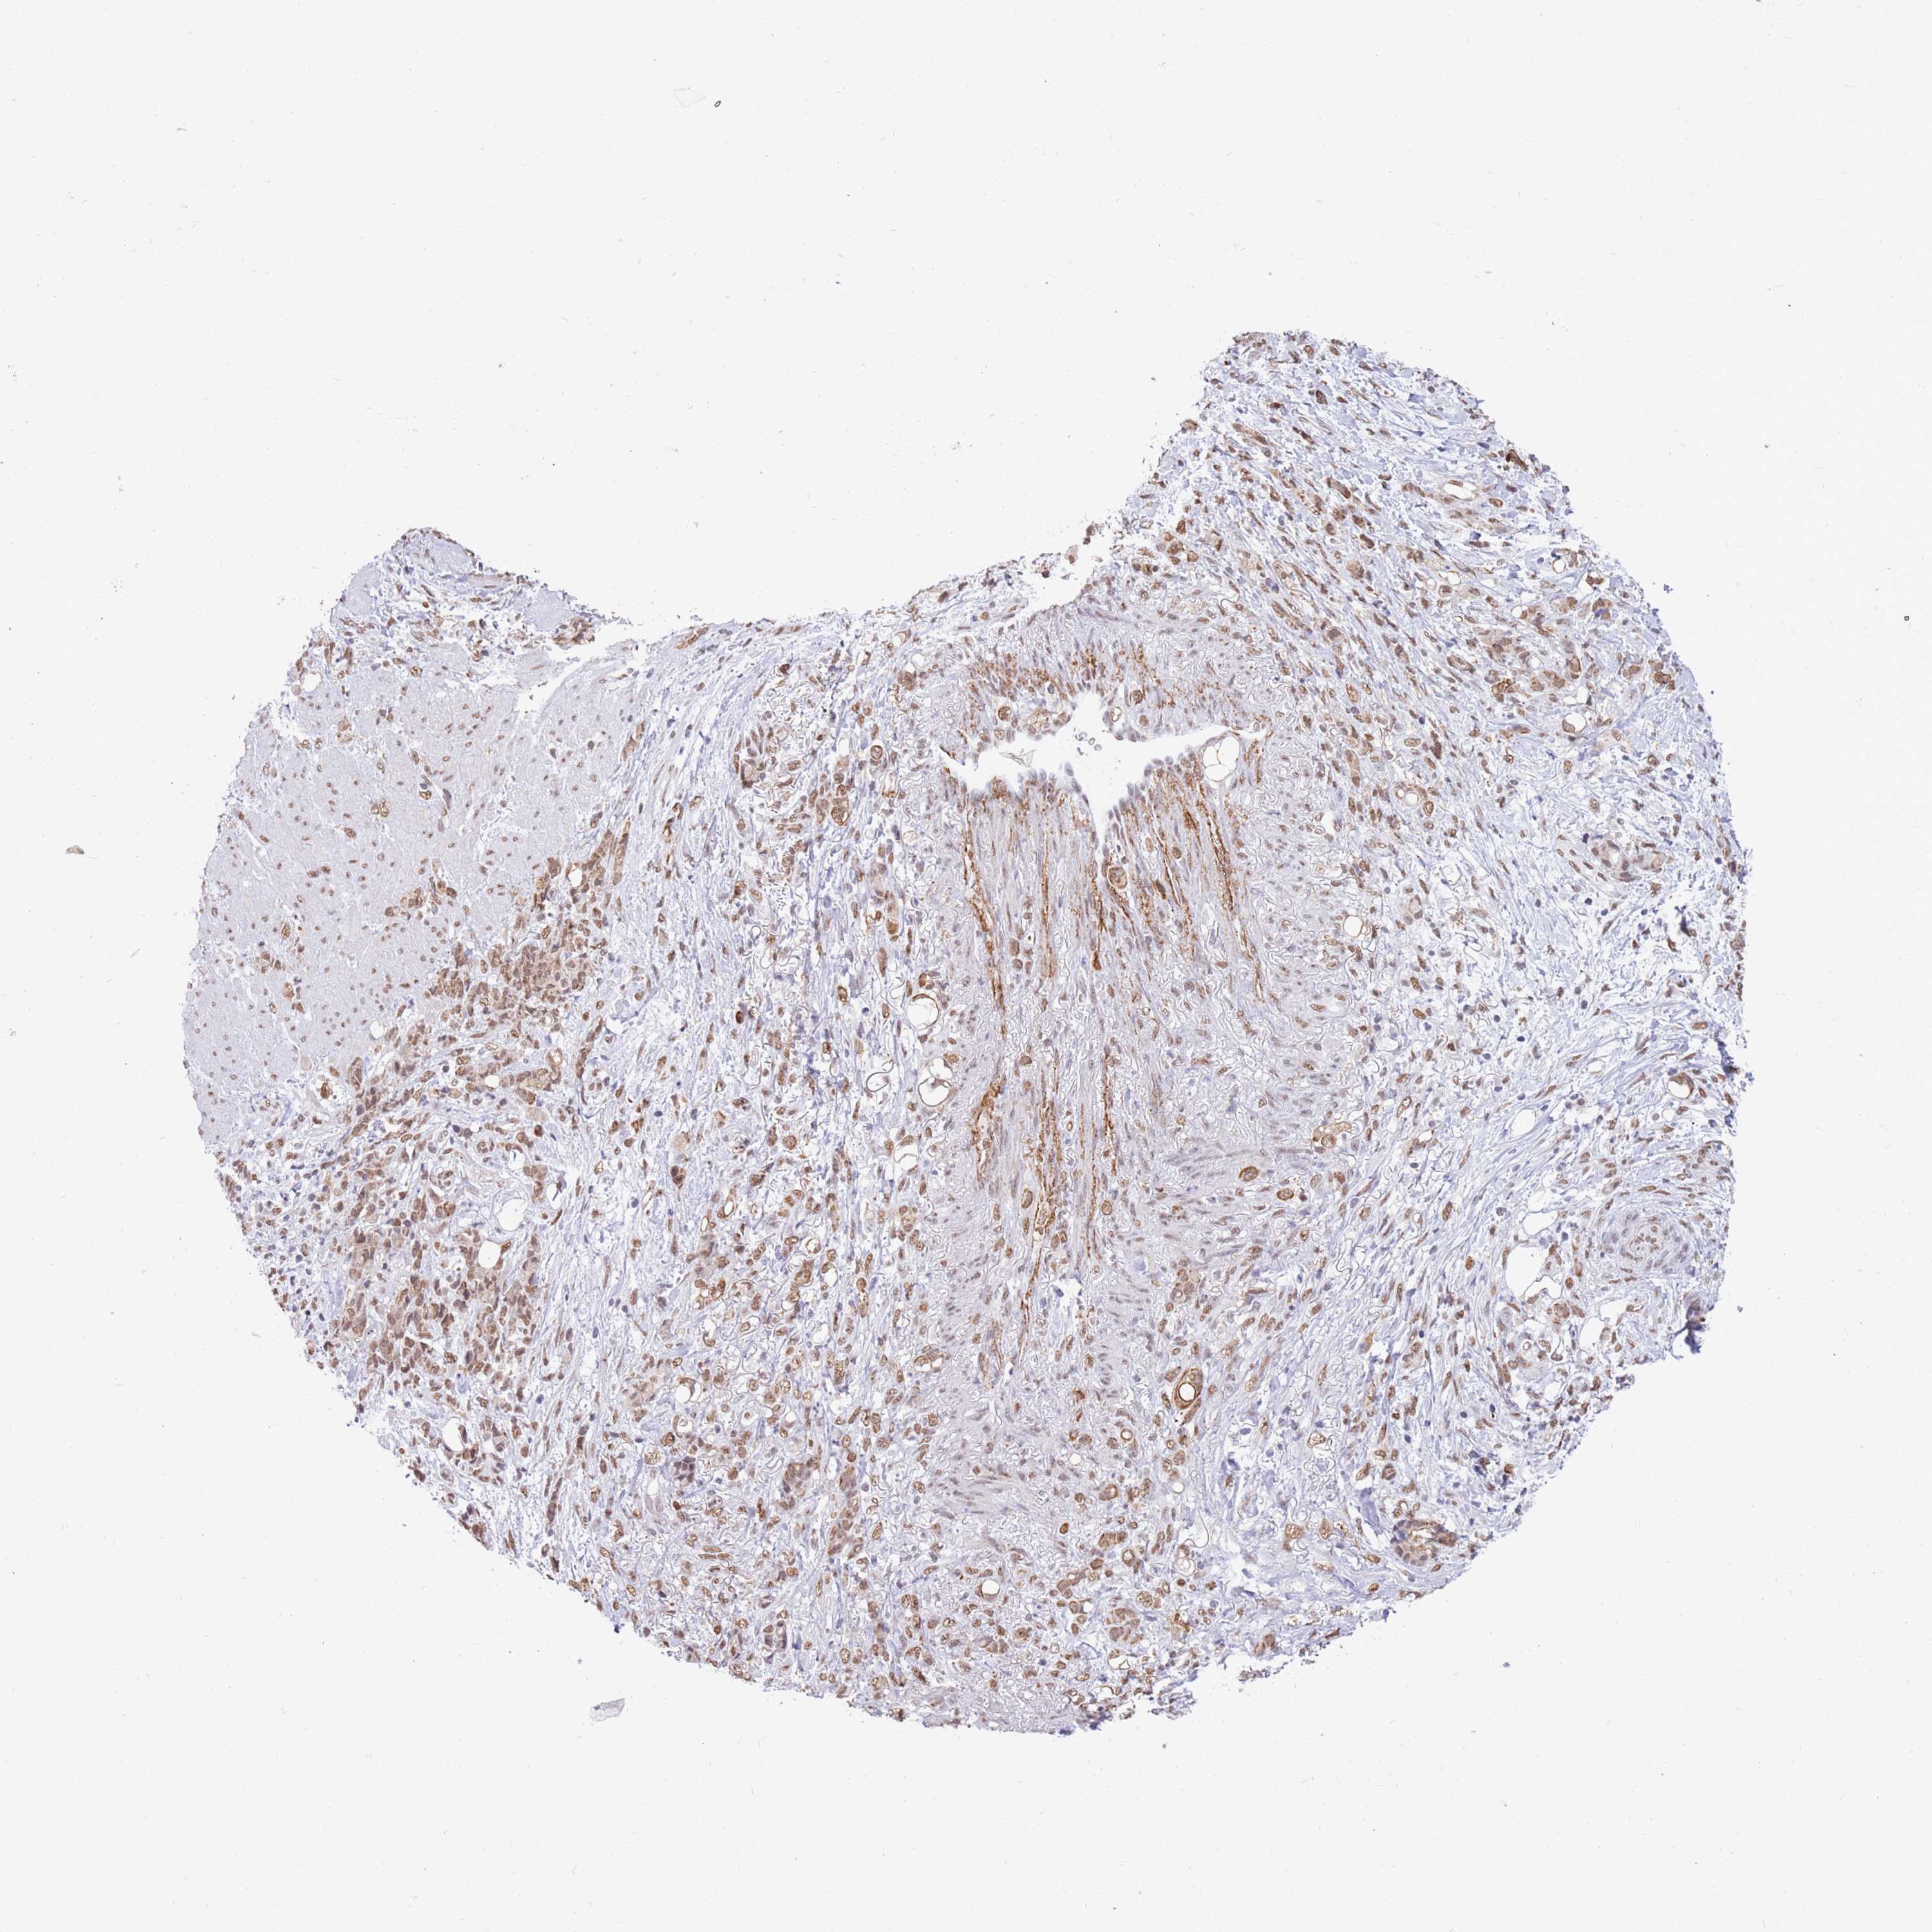

STOMACH CANCER - Protein expressioni

A mouse-over function shows sample information and annotation data. Click on an image to view it in a full screen mode. Samples can be filtered based on level of antibody staining by selecting one or several of the following categories: high, medium, low and not detected. The assay and annotation is described here.

Note that samples used for immunohistochemistry by the Human Protein Atlas do not correspond to samples in the TCGA dataset.

Antibody stainingi

Antibody staining in the annotated cell types in the current human tissue is reported as not detected, low, medium, or high, based on conventional immunohistochemistry profiling in selected tissues. This score is based on the combination of the staining intensity and fraction of stained cells.

Each image is clickable and will lead to virtual microscopy that enables deeper exploration of all samples and also displays staining intensity scores, fraction scores and subcellular localization as well as patient and tissue information for each sample.

Antibody HPA050060

Staining

High

Medium

Low

Not detected

Intensity

Strong

Moderate

Weak

Negative

Quantity

>75%

75%-25%

<25%

None

Location

Nuclear

Cytoplasmic/membranous

Cytoplasmic/membranous,nuclear

Adenocarcinoma, NOS